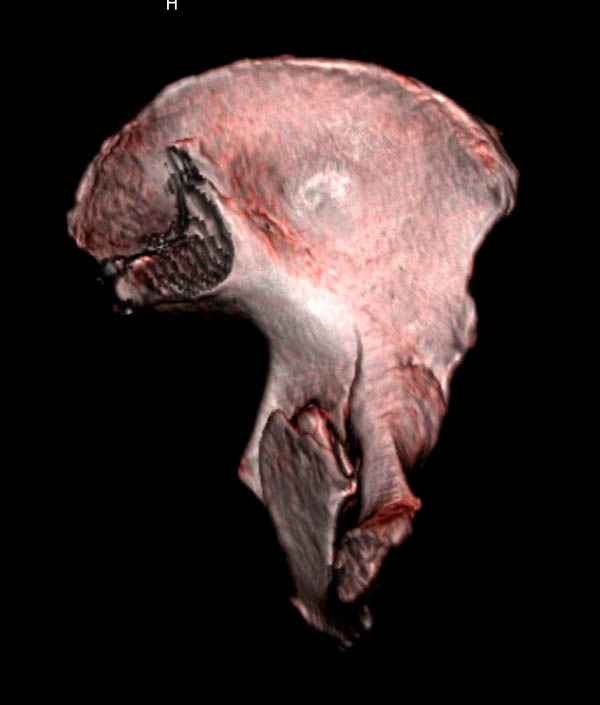

На снимке ацетабулума редко встречающийся очень низкий перелом, наверное, трудно было репозицию через один доступ? Перелом как бы замкнулся в квадрилатеральной поврехности.